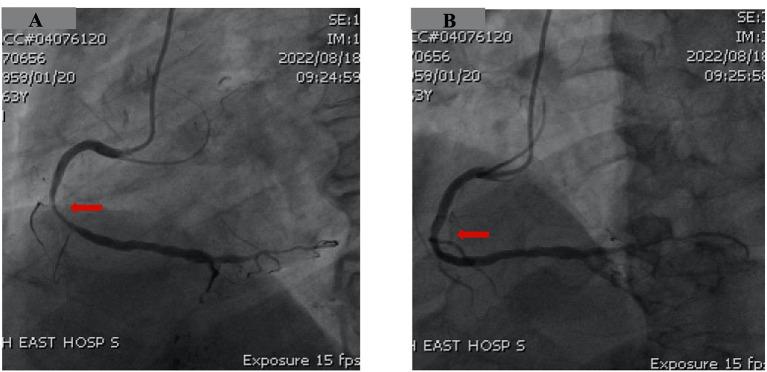

Coronary artery spasm (CAS) may induce lethal ventricular arrhythmia due to severe and prolonged vessel constriction. Tyrosine kinase inhibitors are associated with the occurrence of CAS. Optimal medical treatment is the first-line therapeutic option for the management of CAS, whereas patients who experienced aborted sudden cardiac death (SCD) may benefit from implantable cardioverter-defibrillator (ICD) implantation. We report a case of a 63-year-old Chinese man receiving tyrosine kinase inhibitor treatment for liver cancer who presented with recurrent chest discomfort and syncope with an elevation of high-sensitivity troponin T. Emergent coronary angiography showed sub-total occlusion of the left anterior descending artery without other signs of CAS. Percutaneous transluminal coronary angioplasty with a drug-coated balloon was performed successfully with the guidance of intravascular ultrasound. After 5 months, the patient returned to the emergency room for chest discomfort and another episode of syncope. The electrocardiogram showed ST-segment elevation in the inferior and V5-V6 leads compared to the previous event. Coronary angiography was repeated immediately and showed significant luminal stenosis at the midportion of the right coronary artery (RCA), whereas, after administration of intracoronary nitroglycerine, a remarkable recovery of RCA patency was noticed. A diagnosis of CAS was made, and soon after that, the patient rapidly developed ventricular arrhythmia in the coronary care unit. After successful resuscitation, the patient recovered completely and received long-acting calcium channel blockers as well as nitrates therapy. ICD implantation was performed considering the high risk of recurrence of life-threatening ventricular arrhythmia. During the follow-up period, the patient has been free of angina, syncope, or ventricular arrhythmia, and ICD interrogation showed no ventricular tachycardia or ventricular fibrillation. We first reported the case of a patient with CAS induced by regorafenib treatment complicated with severe atherosclerotic coronary disease who survived from sudden cardiac arrest. ICD implantation is indicated in patients who experienced aborted SCD for the prevention of the next lethal ventricular arrhythmia.

冠状动脉痉挛(CAS)可能由于严重且持续的血管收缩而诱发致命性室性心律失常。酪氨酸激酶抑制剂与CAS的发生有关。最佳药物治疗是CAS管理的一线治疗选择,而经历过心脏性猝死(SCD)未遂的患者可能受益于植入式心脏复律除颤器(ICD)植入。我们报告一例63岁中国男性,因肝癌接受酪氨酸激酶抑制剂治疗,出现反复胸痛和晕厥,高敏肌钙蛋白T升高。急诊冠状动脉造影显示左前降支次全闭塞,无其他CAS迹象。在血管内超声引导下成功进行了药物涂层球囊经皮冠状动脉腔内血管成形术。5个月后,患者因胸痛和再次晕厥返回急诊室。心电图显示与上次事件相比,下壁及V5-V6导联ST段抬高。立即重复冠状动脉造影,显示右冠状动脉(RCA)中段明显管腔狭窄,而在冠状动脉内给予硝酸甘油后,RCA通畅情况明显恢复。诊断为CAS,此后不久,患者在冠心病监护病房迅速发生室性心律失常。成功复苏后,患者完全康复,并接受长效钙通道阻滞剂以及硝酸盐治疗。考虑到危及生命的室性心律失常复发风险高,进行了ICD植入。在随访期间,患者未再出现心绞痛、晕厥或室性心律失常,ICD程控显示无室性心动过速或心室颤动。我们首次报告了一例由regorafenib治疗诱发CAS并合并严重动脉粥样硬化性冠状动脉疾病的患者,该患者从心脏骤停中存活。对于经历过SCD未遂的患者,建议植入ICD以预防下一次致命性室性心律失常。